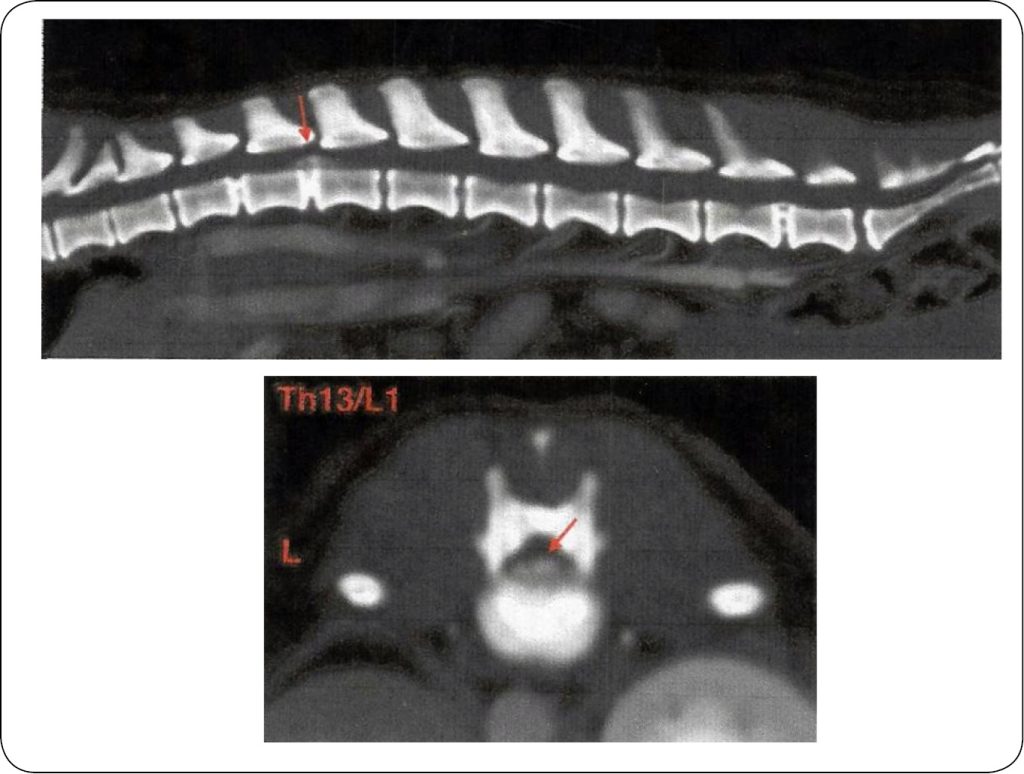

Pacjentką jest pies rasy jamnik szorstkowłosy. Zgodnie z otrzymaną dokumentacją niedowład kończyn miedniczych pojawił się u zwierzęcia po raz pierwszy 18.05.2023 r., dodatkowo były problemy z samodzielnym oddawaniem moczu oraz kału. Wykonano badanie tomograficzne odcinka Th1-S3 (ryc. 1) kręgosłupa, badanie natywne po podaniu dożylnego środka kontrastowego warstwami 0,6 mm. Wyniki ukazały stan po masywnej, dokanałowej ekstruzji jądra miażdżystego krążka międzykręgowego Th13/L1. Masa dysku wykazywała znaczną mineralizację, widoczną na dnie kanału kręgowego od poziomu przestrzeni międzykręgowej do około 1/2 długości L1. Masy układają się centralnie z nieznaczną lateralizacją prawoboczną, osiągając około 75% przekroju kanału kręgowego – podejrzenie ucisku rdzenia kręgowego ciężkiego stopnia. Wymieniona wyżej przestrzeń międzykręgowa nie wykazuje cech zwężenia, aczkolwiek widoczne jest zwyrodnienie dehydratacyjne kmk –częściowa ekstruzja. Dodatkowo centralna protruzja krążka międzykręgowego L7/S –modelująca nieznacznie, dobrzusznie włókna ogona końskiego. Ponadto stwierdzono zwyrodnienie dehydratacyjne krążków międzykregowych na poziomach: C7/Th1, Th2-5, Th7-9, Th12-13, L1-3, L6-7, aktualnie bez cech dyslokacji dokanałowych. Obrys oraz struktura kręgów prawidłowe, mięśnie przykręgosłupowe bez zmian, aorta brzuszna bez cech zatorowości. U pacjentki wykonano zabieg hemilaminektomii Th12-L1 po stronie prawej, usunięto masę uciskającą rdzeń kręgowy. Całość operacji przebiegła pomyślnie, pierwsza rehabilitacja została przeprowadzona w innym ośrodku rehabilitacji zwierząt, doprowadzając pacjentkę do stanu bardzo dobrego oraz wykreowania prawidłowego wzorca chodu (ryc. 2, 3).